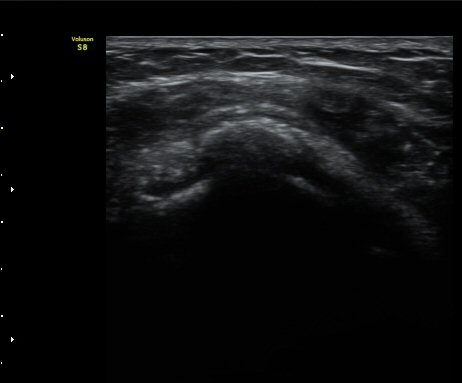

°ßºÀ¿À±¸µ¹±âÀδë Á¾´Ü¸é°Ë»ç¿¡¼­ ÀδëÀÇ ¿ÜÃø¿¡ ±¹¼ÒÀûÀÎ ÀÎ?ºñÈİ¡ °üÂûµÈ´Ù(»çÁø 3).

±Ø»ó°Ç Á¾´Ü¸é°Ë»ç½Ã ±Ø»ó°ÇÀÇ Ç¥Ãþ¿¡¼­ °üÂûµÇ´Â °ßºÀ¿À±¸µ¹±â Ⱦ´Ü¸é°Ë»ç»ó¿¡¼­

ÀδëÀÇ ºñÈİ¡ °üÂûµÈ´Ù(»çÁø 4). ±Ø»ê°ÇÀÇ Á¾´Ü¸é°Ë»ç¿Í Ⱦ´Ü¸é°Ë»ç¿¡¼­ ±Ø»ê°Ç ½ÉÃþ¿¡

Àú¿¡ÄÚ º´º¯ÀÌ °üÂûµÈ´Ù(»çÁø 5, 6).